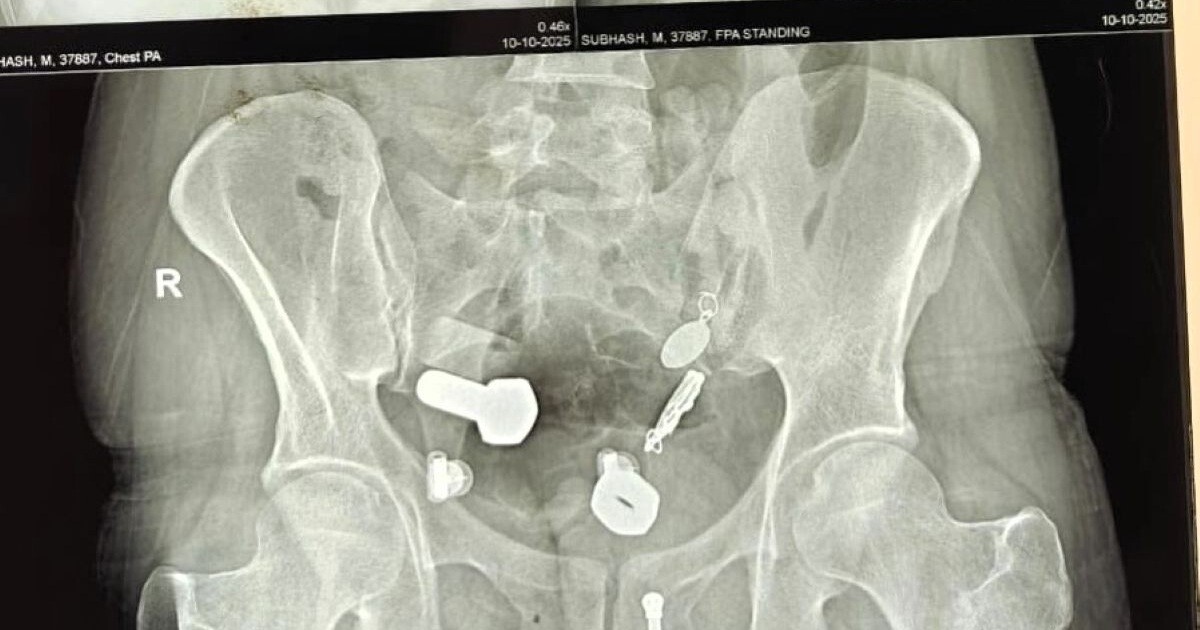

Родственники привезли 34-летнего мужчину в больницу, когда он почувствовал сильную боль в животе и не мог есть и пить. Сканирование показало, что в его пищеводе застряли часы, а в толстом кишечнике оказались металлические фрагменты, гайки и болты.

Врачи обнаружили целую коллекцию в животе пациента.

Хирурги попытались удалить предметы с помощью эндоскопии, но потребовалась полостная операция, она продлилась три часа.

Через небольшой разрез в брюшной полости хирурги извлекли часы и другие инородные тела.

Мужчина поступил в больницу Саваи Мансингх в Джайпуре, Индия, 9 октября. Сейчас он восстанавливается.